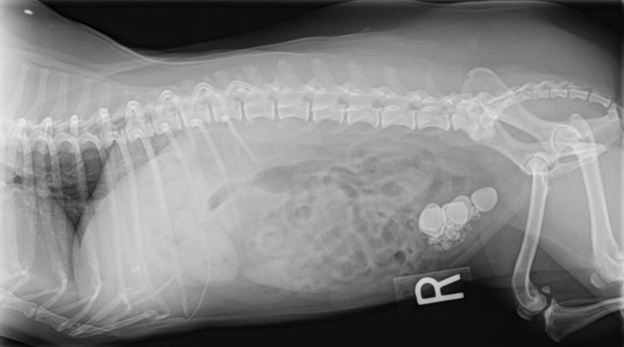

Камни в мочевом пузыре у собак

Чаще всего камни у собак образуются в мочевом пузыре. Они провоцируют раздражение слизистой оболочки мочевыводящих путей, приводя к ее воспалению, а также могут закупоривать уретру (обычно у кобелей), вызывая острую задержку мочи, что уже угрожает жизни собаки.

Наиболее часто встречаются камни, содержащие фосфат аммония, реже – содержащие оксалат кальция, фосфат кальция, ураты, цистин, силикаты. Около 10% камней имеют смешанный состав.

Диагностика мочекаменной болезни у собак